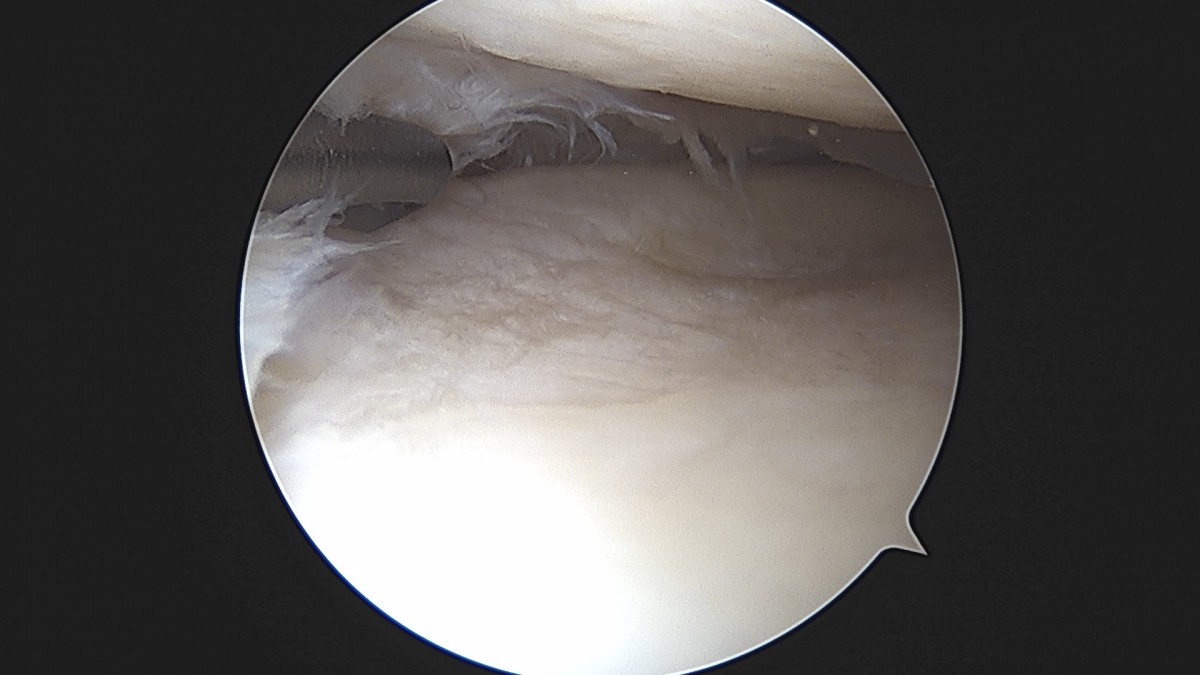

이재상원장님 무릎 반월상 연골판 절제술 최용O 환자

작성자 최고관리자 댓글 0건 조회 379회 작성일 25-09-16 15:57